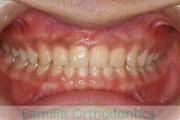

歯並びを治したいということで来院されました。下あごがやや右側に偏位して後退している、上顎前突(出っ歯)でした。上下左右から小臼歯を抜歯して、歯科矯正用アンカースクリューを併用したマルチブラケット法にて治療を行いました。約2年、24回の来院をしていただきました。

下顎の後退はいびきなどの上部気道の障害が出やすいと考えられます。